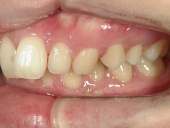

矯正歯科 治療後 右

矯正歯科 治療後 左